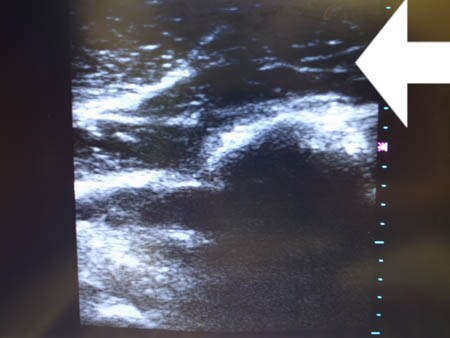

同様に左二の腕 ↓ ↓ ↓

↓ ↓ ↓

さて冒頭でも書きましたが

患者様の皮下脂肪は非常に線維質でした。

つまり例えればヘチマのように

中身は繊維が張り巡らされている状態。

脂肪吸引が非常に非常に!

やりにくい状態です。